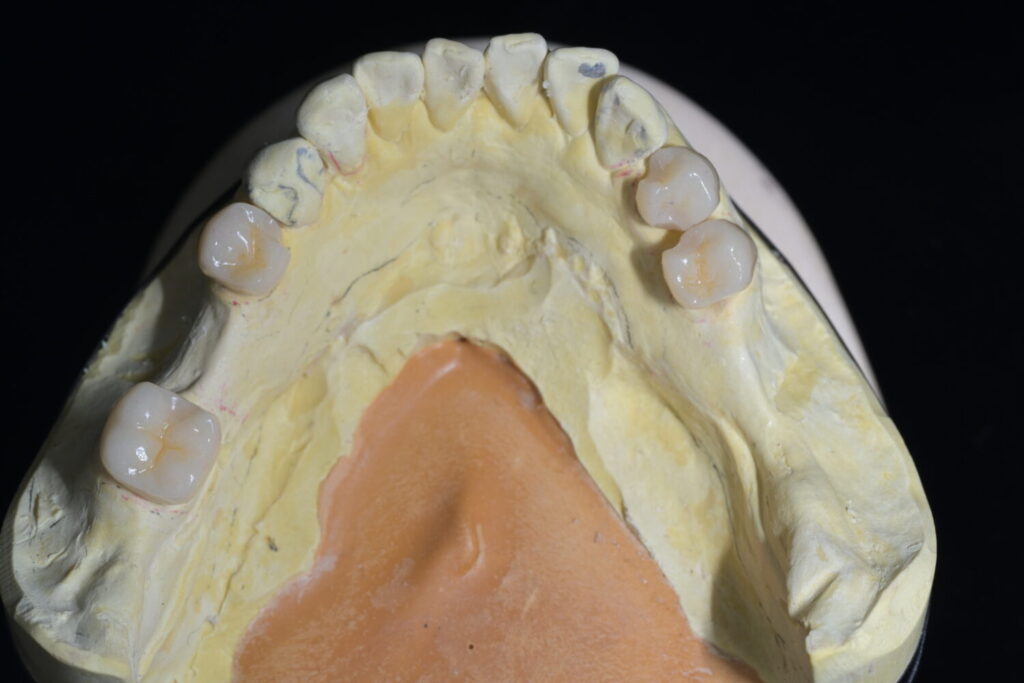

主人の場合、下顎は部分義歯タイプにする事になったので仮義歯を入れる際に、バネをかける歯に特殊な加工をしたサベイドクラウンという補綴物(被せ物)を作成しました。

入れ歯(部分床義歯)のバネ(クラスプ)が装着される歯(鉤歯)に施される、入れ歯の維持・安定を助ける特別な被せ物(クラウン)のことです。設計段階から、バネがかかる歯に対して、適切な掘り込みや面を事前に形成しておくことで、入れ歯がしっかり機能し、快適に装着できるようになります。

口の中のパワーバランスをうまくコントロールするのにとても重要な役割をしてくれるのが「サベイドクラウン」ということです。

このように被せ物にも拘っているのが当院の義歯治療です。